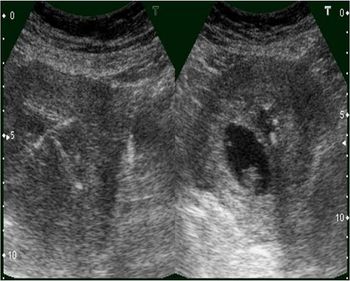

IUCD with Pregnancy IUCD, copper T in uterus with Gestational sacPublished: June 15th 2011 | Updated: